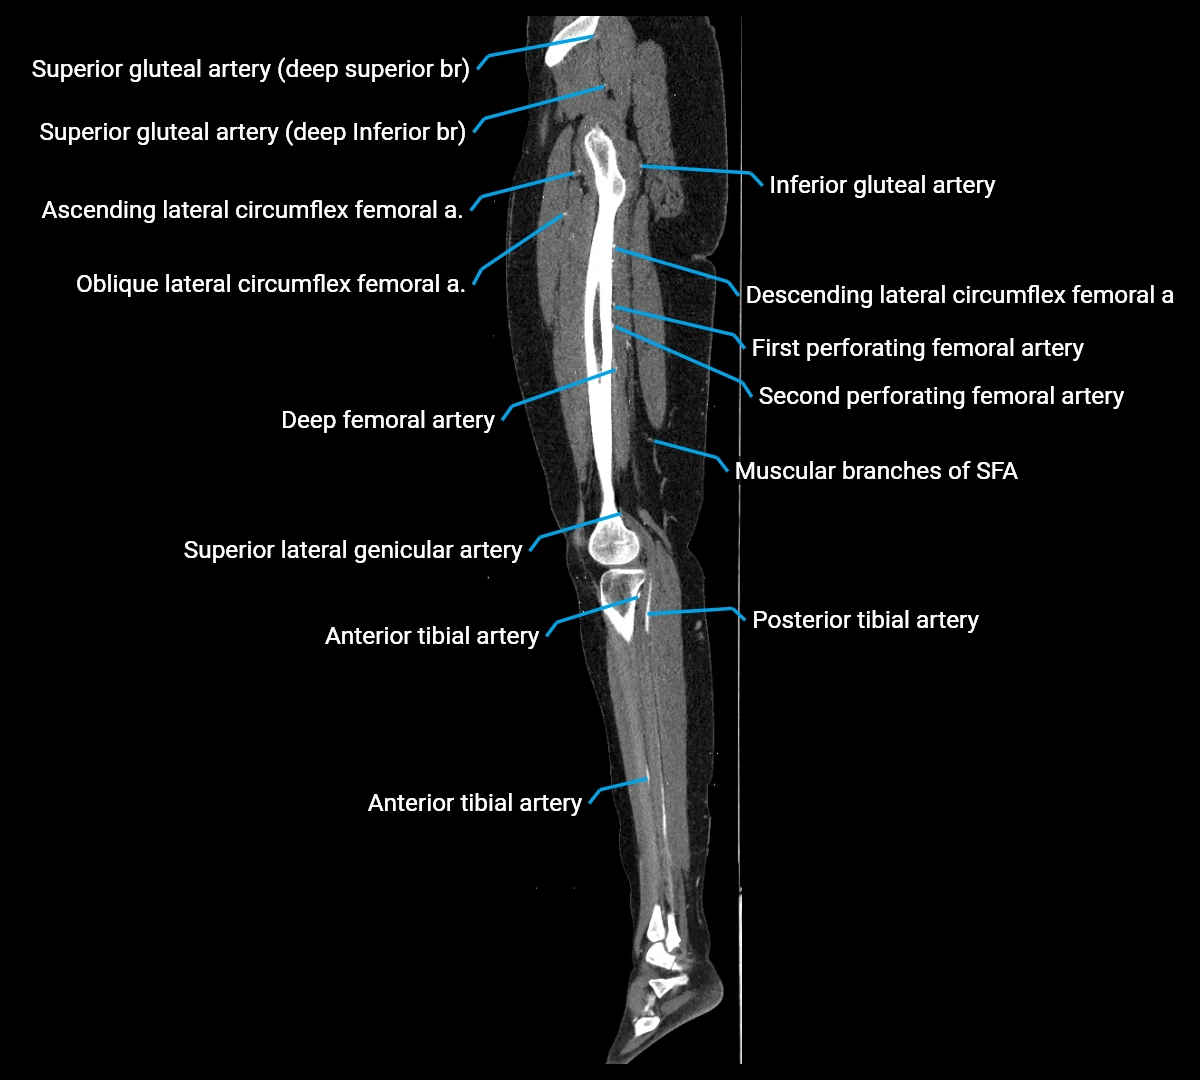

CT images

image